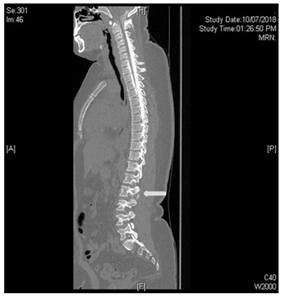

Under the suspicion of intracranial hypotensive headache caused by acute CSF leakage, a CT myelogram was performed Figure 3 the needle was set at L3/4 under radiographic control, contrast was repeatedly injected and x-ray images of lower and upper spine performed. After filling up to the cervical level of the epidural space, the patient’s whole spine was imaged with CT and extravasation was noted Figures 4 & 5.

Figure 3 white arrows pointing to contrast extravasation.